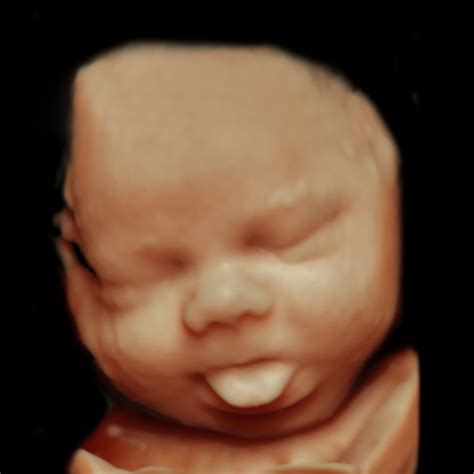

14W Fetus Face 3D

The 14th week of pregnancy is a crucial stage in fetal development. By this point, the fetus has undergone significant changes, and many of its features are becoming more defined. The baby's face, in particular, starts to take shape, with the eyes moving closer together and the ears becoming more prominent. The 14W fetus face 3D imaging technology captures these details with remarkable clarity, providing a detailed view of the baby's facial features.

For a 14W fetus face 3D image, the process is similar, but the focus is on capturing the facial features of the fetus. This requires a skilled technician to position the transducer correctly and adjust the settings to optimize the image quality.